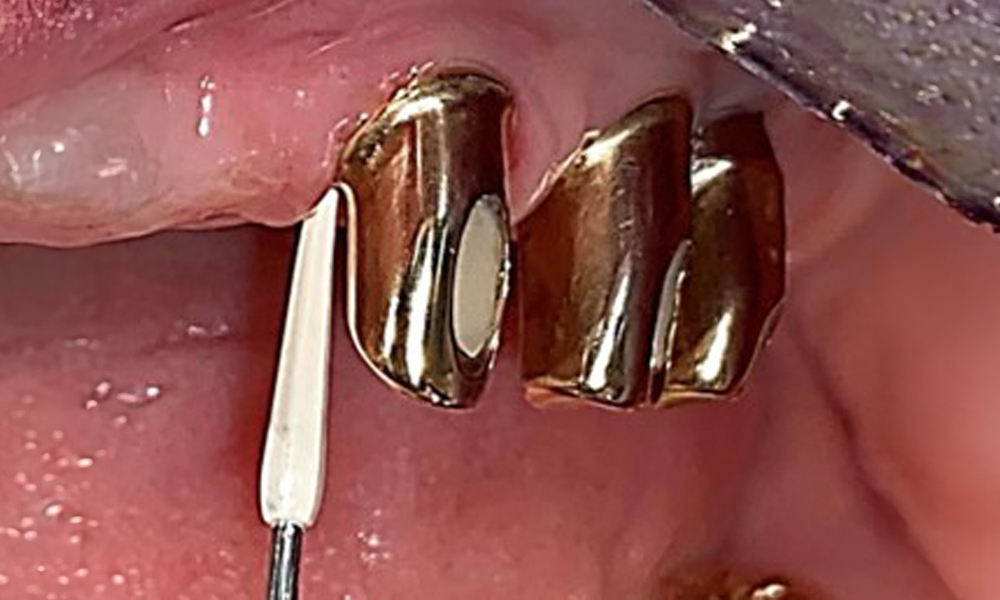

Сондиране на имплант 23 на дълбочина 4 mm с пластмасова сонда, показваща отрицателни резултати от BOP и хиперпластична папила.

Фиг. 6: Сондиране на имплант 23 на дълбочина 4 mm с пластмасова сонда, показваща отрицателни резултати от BOP и хиперпластична папила.

Състоянието на пародонта трябва да се изследва обстойно веднъж годишно. Този преглед осигурява изчерпателна документация за резултатите от пародонталния статус и състоянието на имплантите, включително дълбочината на джобовете, пародонталната рецесия и засягането на фуркациите. Това ще осигури бърза реакция при всяка потенциална прогресия на мукозита, гингивита, пародонтита или периимплантита. Препоръчва се сондиране на импланти с пластмасова сонда. В настоящия случай бе установена мезиална дълбочина на сондиране от 4 mm мезиално от имплант 23. Не бяха открити супурации или кървене, което показва липса на пери-имплантит.